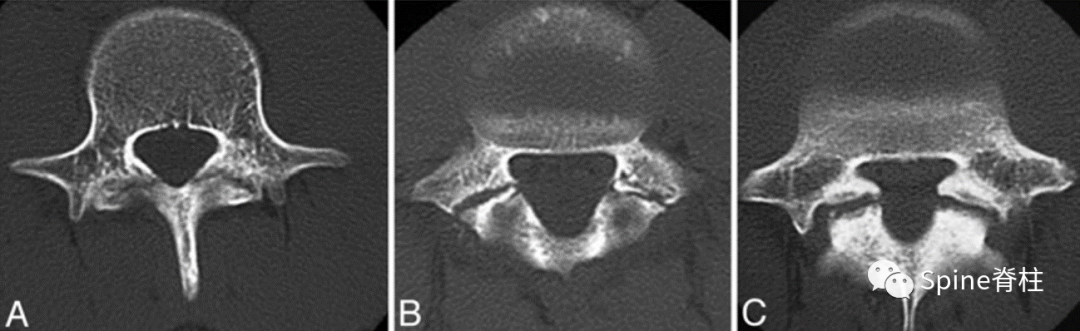

峡部裂的CT分型:A=早期(线性骨折),B=进展期(明显的骨间隙),C=终末期(假关节形成)

图:早期(a),进展期(b),终末期(c)

随后,Sairyo教授进一步CT研究,将Morita分型早期又分为最早期(very early): 骨折线模糊或不连续的骨折线和晚早期(late-early): 骨折线清晰明显。

图:腰5双侧峡部裂,右侧为最早期,左侧为晚早期